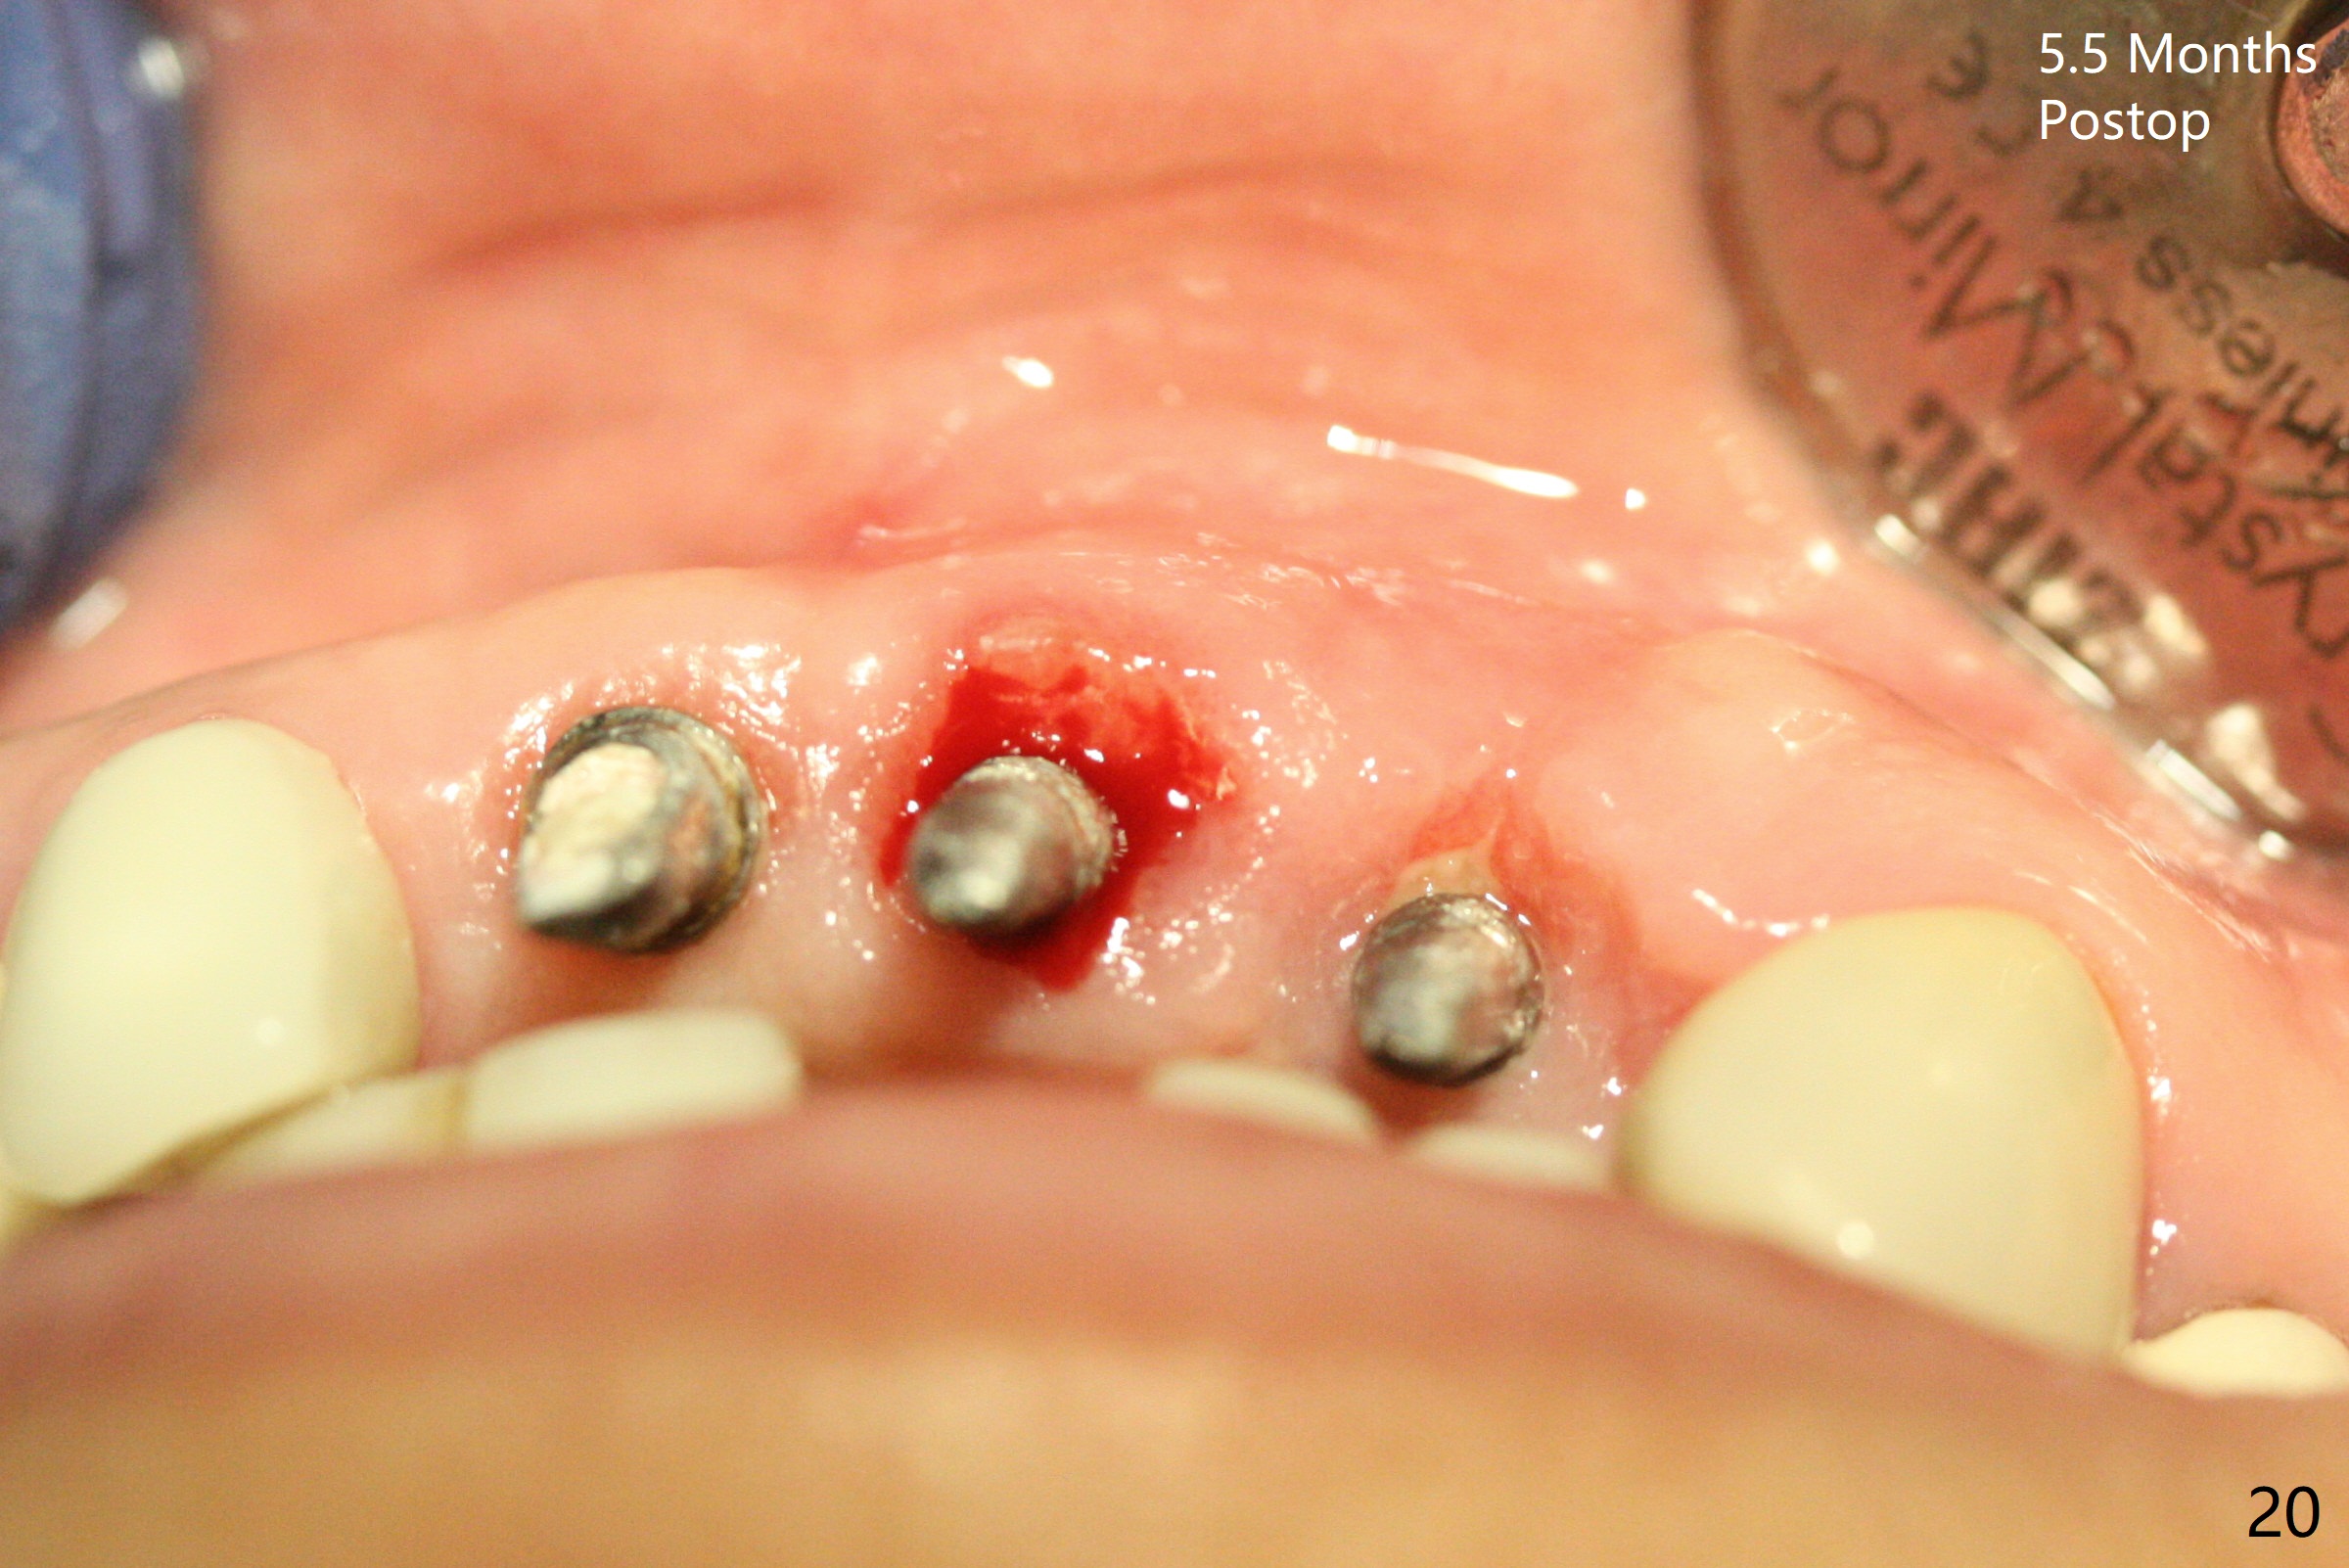

Incision shows exposure of microthreads at #9 and major threads at #10 due to buccal placement (Fig.1). There is bone palatal to the implant at #10 (Fig.2 P), to which a new implant will move. After implant removal, a narrower 1-piece implant (2.5x14(4) mm) is placed palatally at #10 (Fig.3,4) in combination of guide and free hand. At the site of #9 after implant removal, the guide is not used; a 3x17 mm angled 1-piece implant is placed with bad trajectory (Fig.5,6). After re-adjustment (Fig.7), the implant is placed at the right orientation (Fig.8). It appears that the guide is helpful. Allograft is placed mainly buccally (Fig.9,10 *), followed by a piece of collagen membrane (Fig.11). After tension release, flaps are approximated (Fig.12). The buccal gingiva at #9 and 10 recede nearly 2 months postop (Fig.13). Less recession at #9 is associated with more inflammation (Fig.14). The margin of the provisional is adjusted for gingival margin down growth and easy self cleaning with Water Pik (Fig.15). One month later, the gingival inflammation reduces, while there is no obvious buccal collapse (Fig.16,17). Impression is taken after laser gingivectomy nearly 4 months postop (Fig.18). While the gingiva around the implant at #9 is inflamed (periimplantitis?), the gingival cuff at #10 is well formed 5.5 months postop immediately before cementation (Fig.19). The buccal concavity at #10 is minimal (Fig.20). The gingival inflammation at #9 will be hopefully resolved after cementation of the final restorations (Fig.21). There appears to be new bone formation around the coronal implant threads 5.5 months postop (immediately post cementation, Fig.22). The microthreads at #9 may be not covered by the bone, the reason for the gingival erythema. The redness at #10 is asymptomatic 5.5 months post cementation (Fig.23). 粘固后两年牙槽嵴骨质并没有再生(图二十四),说明第一术中植体必须植入骨下(基台部分要长,否则难于修复),第二牙槽嵴处不应该有压力,植入2.5毫米植体,最后钻头应该是2.5毫米,骨下1-3毫米(尝试项目)。